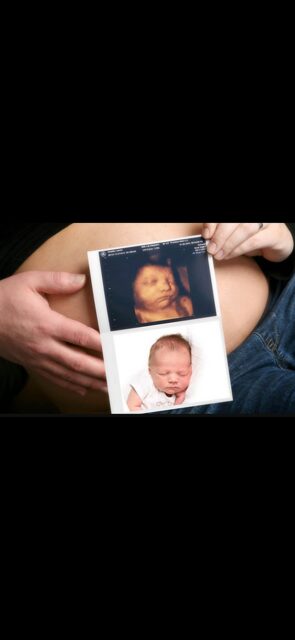

The birth of a new baby is an exciting time for parents, family and friends! At Bonding Moments, we offer a warm family atmosphere that offers Elective 2D/3D/4D and HD prenatal ultrasounds. We use state of the art ultrasound technology that allows our trained technicians to bring your baby to life before your very eyes on an 86 in flat screen TV surrounded by up to 12 of your guests. The realistic images will provide a bonding experience between mommy, daddy, family and friends. See baby yawn, hiccup, smile and kick all in real-time. So, let’s take a journey together and peek inside your baby’s world!

A prenatal ultrasound uses a transducer to deliver high frequency sound waves. Echoes of the sound waves are recorded and transformed into pictures. A gel is applied to the belly and transducer before the scan which helps conduct the sound waves. 2D and 3D are still images .4D adds motion and dimension so it looks like a video and HD adds more realism.